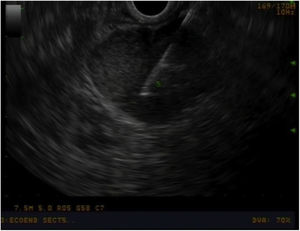

Preoperative study and follow-upAll patients underwent a thorough preoperative study, which included: thoracoabdominal computed tomography (CT) scan, tumour markers (chromogranin A, CA 19.9), complete liver profile, laparoscopy and endoscopic ultrasound to assess the characteristics of the ampulla of Vater and locoregional lymphadenopathies (Image 1), and biopsies. For patients whose diagnosis was uncertain (ampullary neoplasm vs. choledocholithiasis vs. tumour of the head of the pancreas), the study was completed with magnetic resonance cholangiopancreatography and octreotide scan. In patients with jaundice or cholangitis, we tried to avoid preoperative drainage of the bile duct to prevent pre- and postoperative complications14,15 as well as the risk of recurrence.16